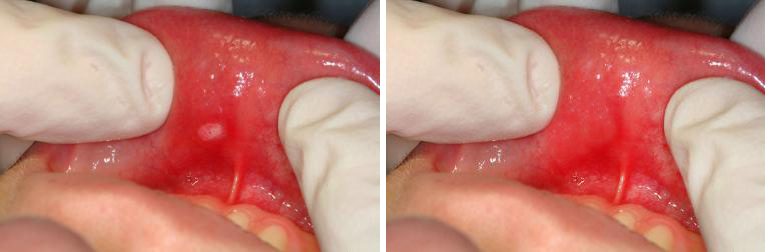

Стоматит при беременности: фото до и после

Первый признак заболевания — появление болезненных язвочек на слизистых оболочках десен, щек, мягкого неба и губ. Язвочки выглядят как белые пятна с красной каймой. Внешнее проявление стоматита сопровождается болевыми ощущениями и чувством легкого жжения во время принятия пищи.